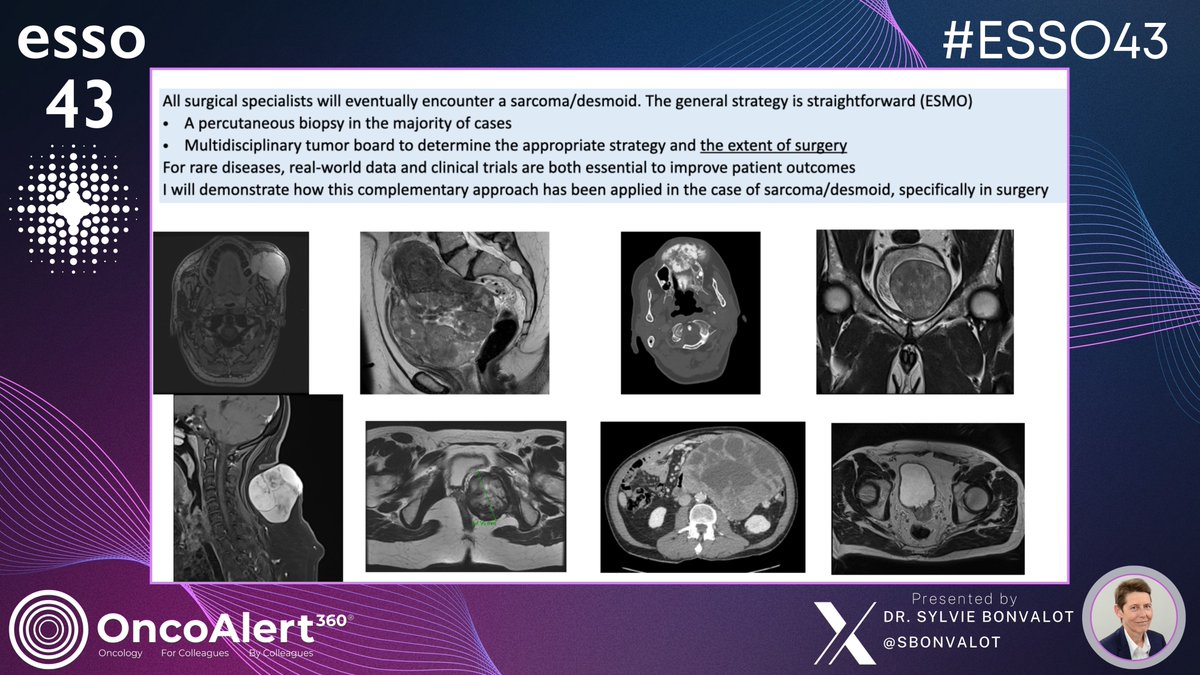

The @OncoAlert 🚨Coverage #ESSO43 DAY ONE Life Time Achievement Award Lecture🏆 Contributing to the enhancement of sarcoma patient care, a shared challenge for specialists across various disciplines Speaker: Dr. Sylvie Bonvalot🇫🇷 @SBonvalot All surgical specialists will